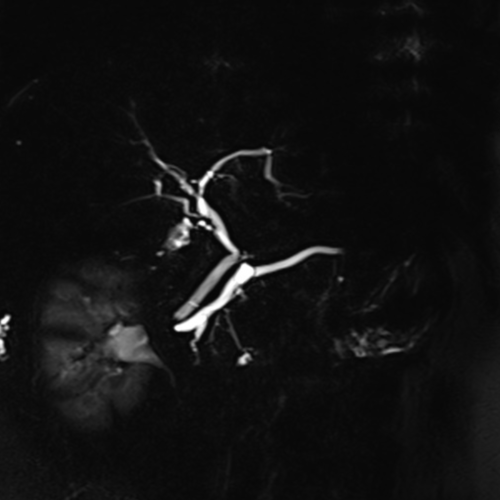

Cet examen est réalisé pour analyser les voies bilaires, la vésicule bilaire, le canal de Wirsung.

Cette examen permets d’analyser les voies bilaires intra et extra hépatique, et le canal de Wirsung. Il permet de diagnostiquer les cancers, cholangiocarcinoms, TIPMP, calculs biliaires, pancréas divisum.